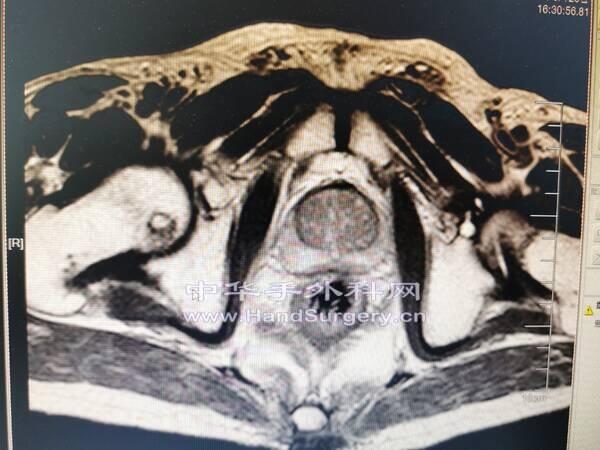

肛肠肿瘤患者,行盆腔核磁检查无意间发现股骨头肿物

囊肿影像局限,孤立,不在负重区,暂不考虑骨坏死。

会诊意见:考虑孤立性骨囊肿,不除外转移